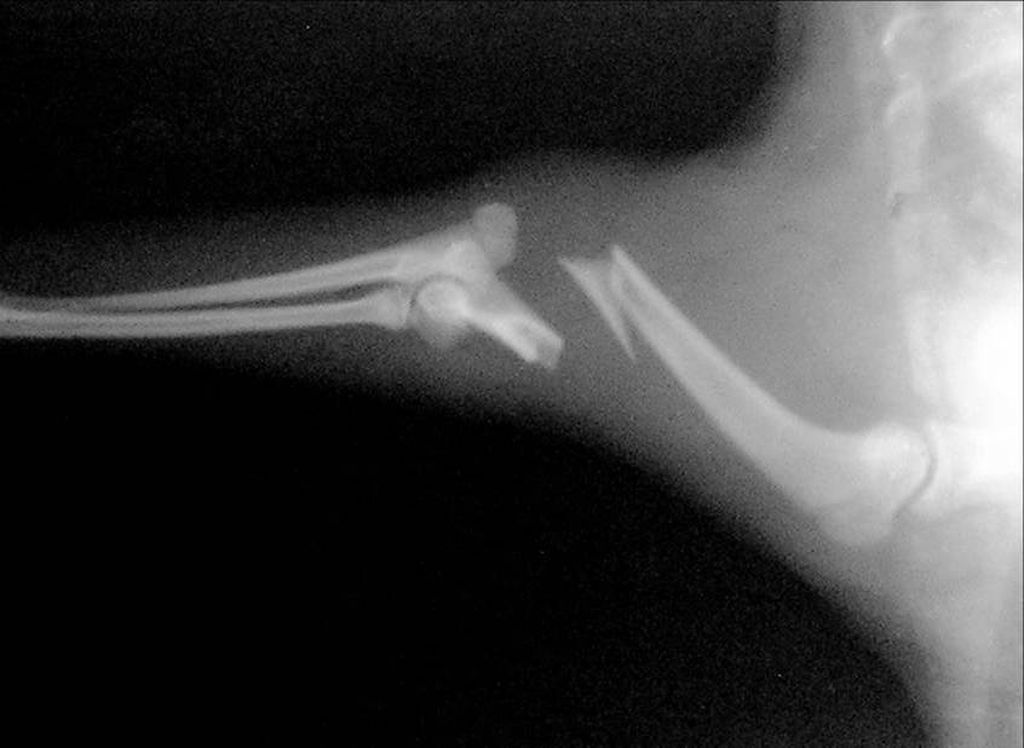

Рентген хорош тем, что снимки можно выполнить без наркоза и быстро получить дополнительную информацию о травме. Не везде есть цифровой рентген, но без обычного аппарата уже не обходится ни одна мало-мальски приличная ветеринарная клиника.

На снимках будут видны опухоли, переломы и смещения позвонков. При сильных травмах на основании рентгена можно утверждать факт разрыва спинного мозга (сочетание перелома и вывиха позвоночника). Однако само нервное вещество на рентгене не увидишь. Поэтому если владельцы готовы на хирургическое вмешательство и хотят сделать все возможное, кошке предстоит специальная диагностика.

Если животное постоянно держит больную лапу на весу, совсем на нее не опираясь, то это указывает на перелом или трещину кости. Питомец не позволит дотронуться до больной конечности и будет агрессивно защищать ее при любой возможности осмотреть. Обычно кошка старается все время находиться без движения — так болевые ощущения хоть немного уменьшаются. Если приглядеться внимательно, то будут заметны отечность конечности и повышение локальной температуры — поврежденная лапа станет горячей. Данная ситуация требует срочного вмешательства.

Больную лапу нужно обездвижить, но если у хозяина совсем нет навыков подобных перевязок, то необходимо аккуратно доставить питомца в клинику, стараясь не прикасаться к поврежденной части тела. Нужно использовать для этого переноску, так как нельзя тревожить больную конечность, а в таком состоянии животное может испугаться и резко вырваться. Специалисты проведут осмотр и сделают рентген. Это позволит установить, какая именно кость повреждена и насколько сильно. Потом на лапу накладывают тугую повязку, лангетку или гипс — выбор осуществляется исходя из серьезности травмы. Коту необходимы постоянный покой, правильное питание и тщательный уход, пока лапа полностью не заживет.

При переломах и вывихах у животного наблюдаются общие клинические признаки: болевой синдром, нарушение двигательной функции (хромота), отечность поврежденного места.

Переломы бывают трех видов — закрытые, открытые, со смещением. К серьезным повреждениям относятся и трещины.

Для закрытого перелома без смещения характерны следующие симптомы: сломанная кость находится в привычном положении, кожные покровы и ткани отекают, синеют, краснеют. При переломе со смещением кость расходится в разные стороны, мягкие ткани повреждены частично. Существует опасность внутреннего кровотечения.